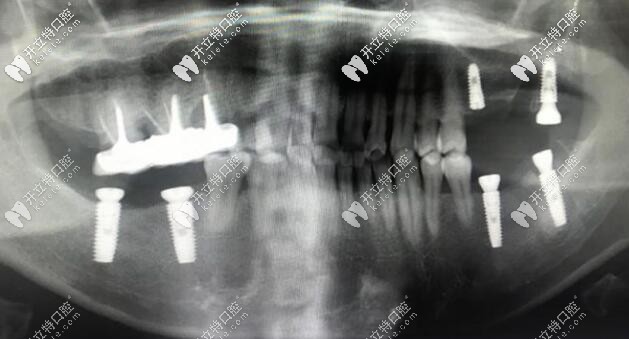

本身我的牙齒從小就不好, 已經(jīng)補(bǔ)的不少顆牙齒了,到現(xiàn)在有時(shí)候吃東西都會(huì)掉一塊,給你看一下我的牙齒一共缺失五顆,除了下邊兩邊后牙連續(xù)兩顆外,上牙也有一顆缺失,現(xiàn)在都有些不知道該怎么辦了。

右下就比較簡(jiǎn)單,就是缺兩顆種兩顆;但左邊的情況就比較復(fù)雜,不僅有殘根齲壞的智齒,但是后面的骨頭還算是好的,醫(yī)生的建議是上下各種兩顆,但是用三顆牙冠修復(fù)。

我看了一眼時(shí)間:6顆種植體不到半個(gè)小時(shí),平均一顆不到十分鐘,這個(gè)速度是佩服的。

這種植后的樣子的,當(dāng)然種牙的第二、三步還沒做的,但是我想比較困難的已經(jīng)完成了, 后面帶牙冠只要聽醫(yī)生的就好啦!